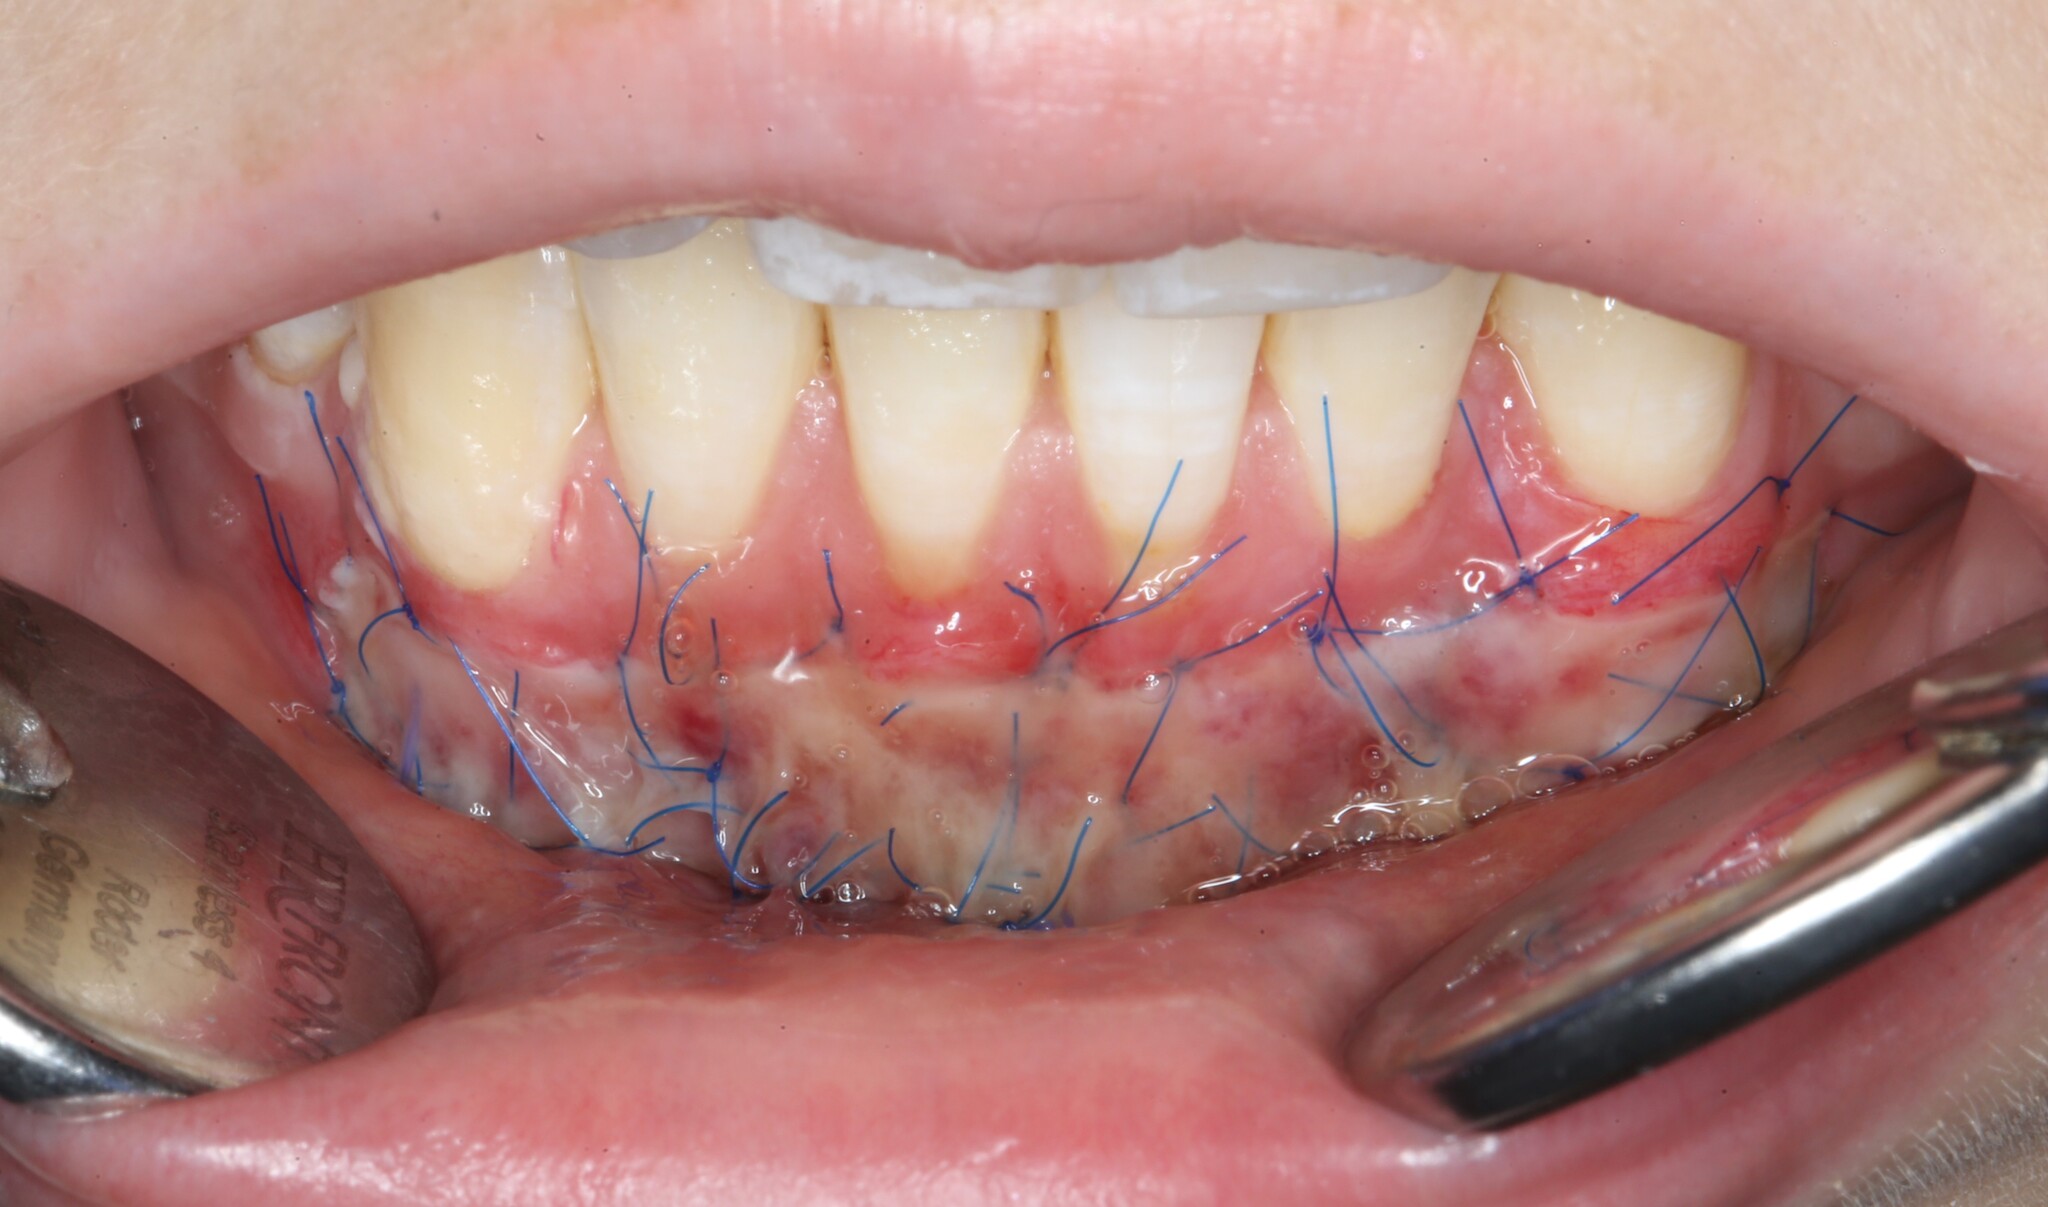

Операция закончена – ничего сложного нет:

Правда, от количества швов меня трясет. Если вам когда-нибудь было интересно, что в своей профессии я не люблю больше всего, так это наложение швов. Для пациента в этом тоже нет ничего приятного. Швы сильно натирают нижнюю губу - приходится меньше разговаривать и больше молчать.

Осмотр через пару дней:

Рана покрывается фибрином, белком, чьё наличие говорит о нормальном заживлении раны. Счищать его не нужно!